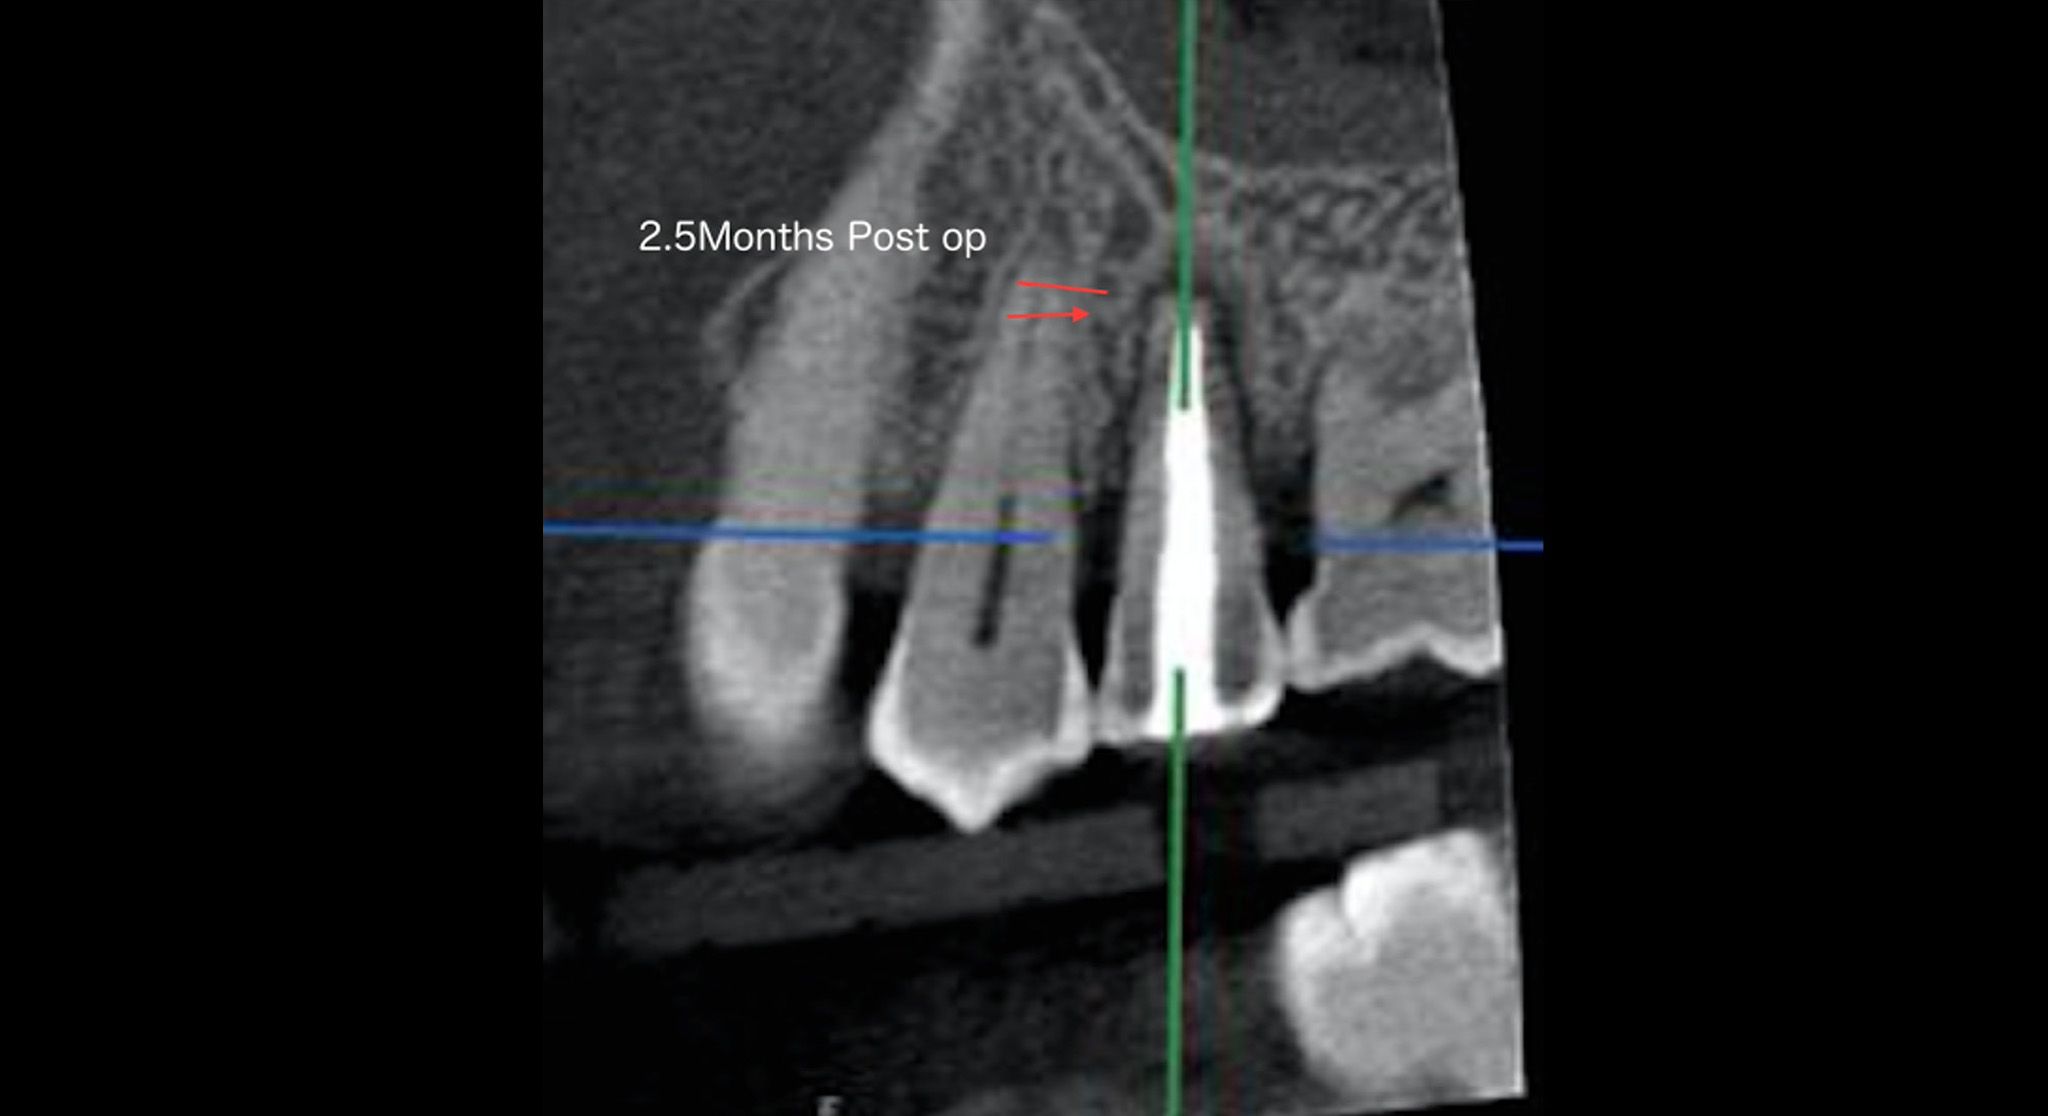

| 治療内容 | 歯周病の検査でポケットを測定する時に歯周ポケットがあるからといって必ず歯周病だと診断することは危険です。その理由は歯の内部が細菌感染を起こしてその結果、根の先に膿がたまり膿は組織の弱いところから外に出ようとするために歯と骨の間にある歯根膜という部分から外に向かって排膿しようとして歯周組織が破壊され、あたかも歯周ポケットを形成するように見えるからです。つまり歯周ポケットがあるからといって必ずしも歯周病ではないということになります。もし、診断を間違えて歯周病の治療であるポケットを綺麗にする掻爬術を行ったとすると、歯の表面にあるセメント質を剥ぎ取ってしまうので歯周組織である歯根膜・骨は二度と再生致しません。そのような意味で診断がとても重要になります。こちらの患者様は歯頚部に力により欠損が出来てそこから歯の内部に細菌感染がおこり歯髄がダメージを受け根先端が化膿して排膿を起こして歯周ポケットのような排膿路が出来た症例です。2.5ヶ月にCTを撮影して治癒を確認致しました。骨が見事に再生していることに注目して下さい。根管治療が成功した結果、排膿路が消え歯周ポケットがなくなりました。 |